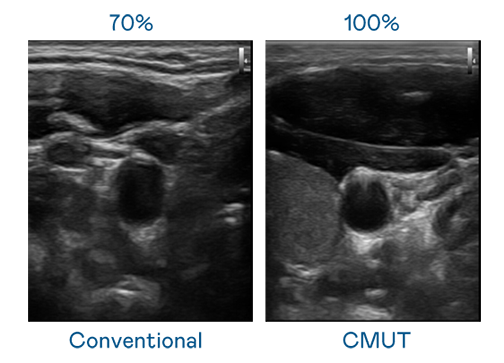

CMUT 技术是一种用电容式微机电元件来产生超音波讯号的技术。与传统 PZT 压电式技术相比,CMUT 频宽增加 30%,更宽频的超音波讯号让影像解析度大幅提升,是实现高影像品质医疗超音波扫描、促进精准医疗发展的关键技术。

超音波影像的解析度高低,首先取决于探头能发出的讯号频宽。713贵宾会 CMUT 可提供高清晰的超音波讯号,提供高频宽、高灵敏度、影像纹理细节更高的超音波影像,协助医护人员缩短影像判读时间及利用精准的医疗影像进行诊断。